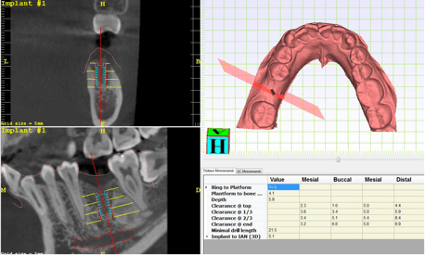

在斷層掃描的 3D 圖疊合牙齒的掃描圖,即可在疊合圖上設計植牙的位置,以此輸出的導引板上設有卡準,植牙器械順著這個卡準,植牙位置超精準,手術速度也會快很多,更能避免傷到重要的神經血管,安全、快速、舒適一次到位。